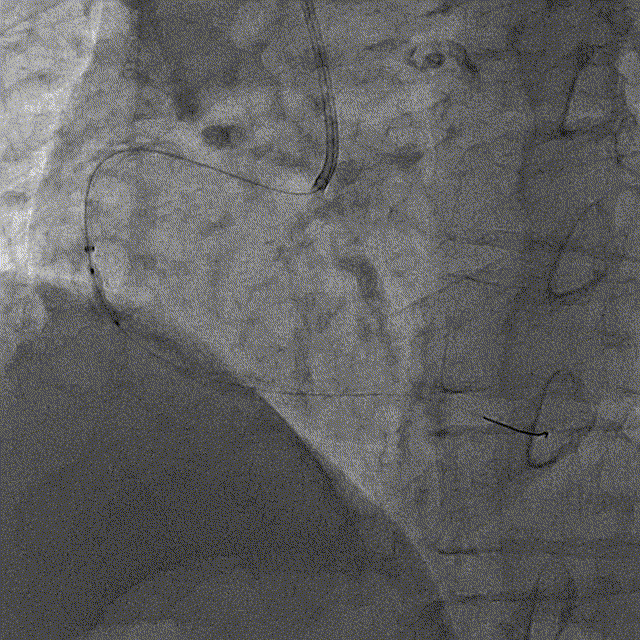

冠脉造影

冠脉造影结果:LM外膜钙化,内膜不光滑,中段狭窄90%,TIMI3级。LCX外膜钙化,内膜不光滑,TIMI3级。RCA外膜钙化,内膜不光滑,近段狭窄80%,中段狭窄90%,可见破损斑块,TIMI3级。